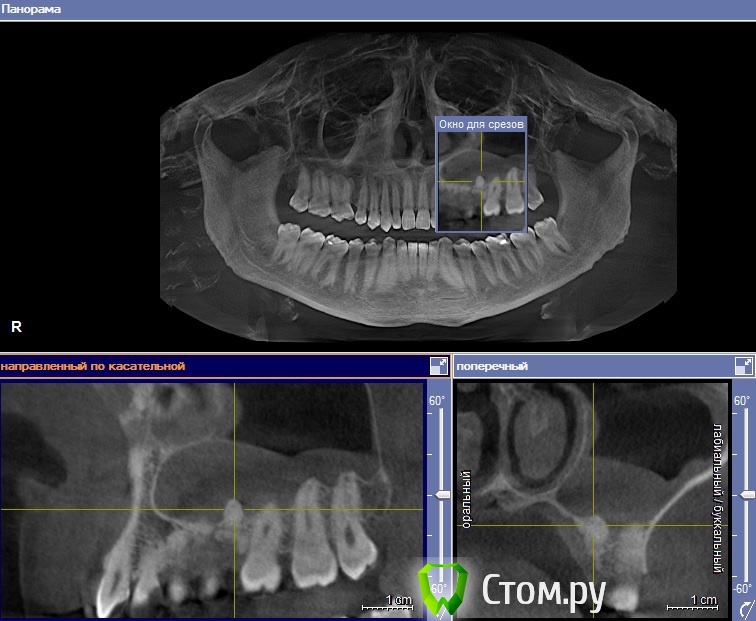

fmn Опубликовано 2 августа, 2014 Поделиться Опубликовано 2 августа, 2014 Здравствуйте! Пациент не мой, коллега попросила выложить этот случай на обсуждение, так как есть определённые затруднения с диагнозом. Из анамнеза - хронический гайморит. В качестве находки - симметричные новообразования между корней 5 и 6 зубов верхней челюсти. Смущает связь с изменениями в слизистой оболочки верхнечелюстного синуса. ЗЫ Сорри за нарезку - Галилеос самый мой нелюбимый просмотрщик. Если нужно, могу выложить архив с КТ.Какие мысли по диагнозу и тактике? Ссылка на комментарий

fmn Опубликовано 2 августа, 2014 Автор Поделиться Опубликовано 2 августа, 2014 Спасибо за ответы. Там все зубы присутствуют, я просто плоскость среза выставил через эти штуки, и она прошла более нёбно. Ссылка на комментарий